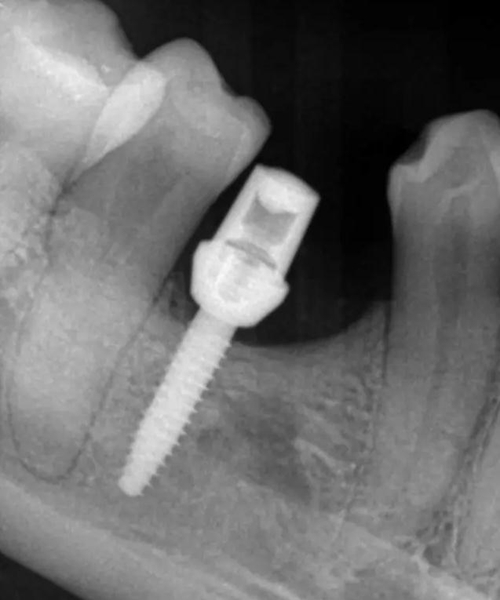

偏遠中植入。 術后病人恢復良好, 無感覺異常。

三個月后上基臺